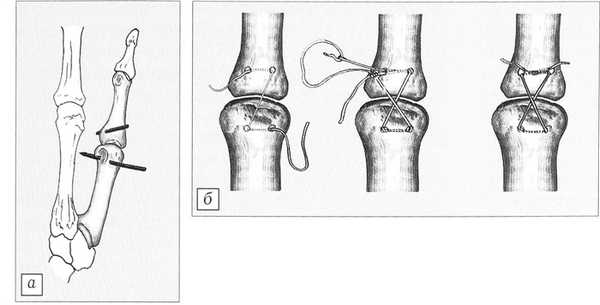

Рис. 2. В I пястной кости и основной фаланге сформированы каналы (а). Через каналы проведен рассасывающийся материал «полисорб», узел погружен внутрикостно (б).

При сохранении структуры связки в случае отрывов подшивали связку поднадкостнично к месту прикрепления П-образным швом нерассасывающимся материалом «этибонд» 5/0, в случае разрывов накладывали швы на саму связку. Апоневроз восстанавливали. При выраженном удлинении связки за счет регенерата после проведения через внутрикостные каналы материала «полисорб» выполняли пластику локтевой коллатеральной связки по Neviaser [7]: из апоневроза или капсулы сустава выкраивали Z-образно два лоскута, создавали дупликатуру, лоскуты перемещали дистально и фиксировали поднадкостничным швом. Выделенную часть расщепленного апоневроза подшивали к месту прикрепления связки. Производили укорочение регенерата сухожилия короткого разгибателя I пальца по типу гофрирования.

Доступом к лучевой коллатеральной связке служил S-образный разрез по тыльно-лучевой поверхности, ход операции был аналогичен описанному выше.